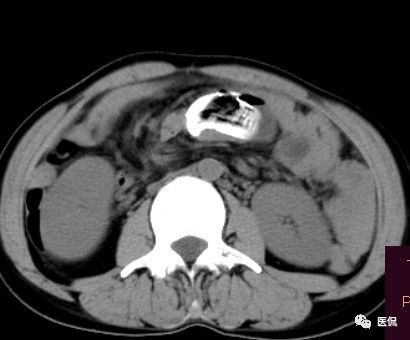

影像特点

腹腔内残留的纱布在人体内引起渗出或液化坏死并纤维包裹形成异物性脓肿(纱布瘤)。纱布瘤的影像特点:圆形或卵圆形肿块,较大,有完整包膜,薄壁,较少的情况下为厚壁,边界较完整,增强后薄膜可以持续强化。不同时期的纱布瘤可以有不同表现:早期(10个月或半年内)多表现为蜂窝状;2~5年内一般表现为囊性飘带状;10~20年之后则为实性软组织密度,包膜钙化呈钙化网状结构。手术过程中残留在人体内的医用纱布所形成的肿瘤样病变。

腹腔内遗留纱布团的影像学表现,以B超较具特征性,其主要表现为:腹腔或盆腔内特殊率减的黑色包块,后方伴有扇形衰减的声影,上窄下宽,好似一“黑色大布”,早期包块内含有不规则光团或光点,随时间延长有缩小或消失,为纱布团内气体。CT的优势在于早期常表现为软组织密度的肿块,其内可见多少不等的气泡,随时间的延长气泡逐渐被吸收减少至消失,增强扫描可见包膜不同程度强化而内容物无强化。熟悉其影像学表现,可在术前作出明确诊断。